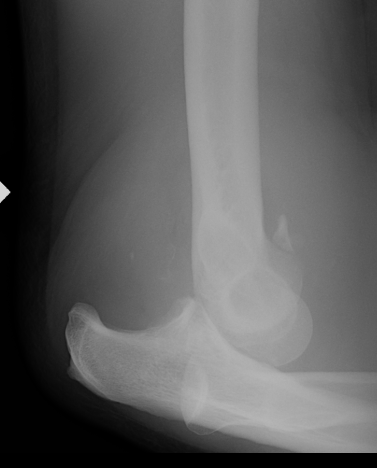

Ulna collateral ligament injury

6 /100 000

- second most common dislocation after shoulder

FOOSH